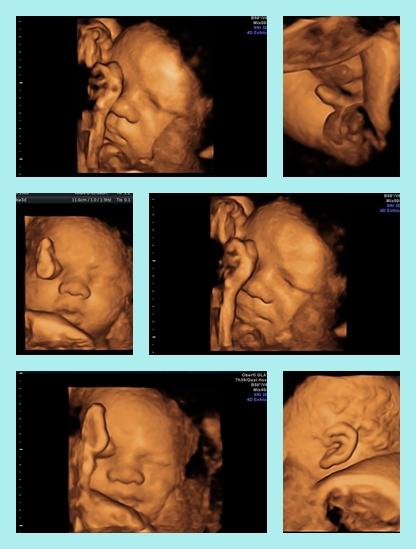

oh man das ist ja auch so gar nicht nett mit deiner Schwiegermutter. naja so ähnlich läuft es bei uns ja im Grunde auch. ich finde es so schlimm das sich Großeltern so extrem auf ein Geschlecht fixieren. es ist doch nicht denen ihr Leben. die hatten doch viele Jahre Zeit zum Kinder kriegen und sich Geschlechter wünschen. unser eins ist einfach nur dankbar ein hoffentlich gesundes Baby im Bauch zu haben und die sind so vermessen. ich meine ihr hattet einen langen und sicher steinigen Weg, ich habe genug durch den Job gesehen und erzähle da ja auch gelegentlich von - unsere Familien sollten doch eigentlich wissen das das Geschlecht ganz schön unwichtig ist! Auch wenn sie diese Sprüche vielleicht nicht so meinen, es ist verletzend und irgendwie respektlos finde ich :-( ja die Bilder sind wirklich toll und faszinierend. in meiner ersten Schwangerschaft war ich mal notfallmäßig bei einer vertretungsärztin. die hat dann plötzlich auf 3d umgestellt. da war ich so naff. hatte nie viel auf solche Bilder gegeben. jedenfalls bekam ich diese Fotos nicht ausgedruckt, ich war so enttäuscht und frustriert das diese wildfremde Person die "ersten Fotos" MEINES Kindes besitzt und das ich die nicht mal meinem Mann zeigen konnte. jedenfalls hab ich mich echt gequält und dann beschlossen für 60 € einen ganz offiziellen 3d Schall machen zu lassen. habe alle Bilder und Videos auf einen Stick bekommen. das war dann bei 37+0. da sieht man meistens ja nicht mehr so viel weil die kleinen kaum noch Platz haben und zu tief im Becken liegen. aber ich hatte ohnehin recht viel fruchtwasser und Felix ist erst unter der Geburt ins Becken gerutscht, so hatten wir eine tolle Sicht. die ganzen Arzthelferinnen wurden nach und nach zum gucken rein geholt weil die Ärztin sagte so spät sieht man selten er Kind so gut. hänge mal was dran

Ja da hast du recht finde es auch respektlos und bin auch wütend mein freund meint dann immer ich soll das nicht ernst nehmen leichter gesagt als getan... Ja der weg war echt nicht einfach aber ich hab nicht aufgegen und jetzt darf ich dieses wunder endlich erleben und genießen freue mich schon extrem auf die zeit ;-) Wollte auch bei diesen ultraschall einen 3d haben aber meine ärztin meinte es ist besser beim nächsten termin das zu machen aber wo ich jetzt deine maus gesehen habe .... Aber naja muss ich mich noch gedulden. Hoffe das es auch so schöne bilder werden. Wahnsinn wow die fotos von felix sind ja der wahnsinn!!!!!! Also so eine gute qualität hab ich ja noch nie gesehen.... Hab mir auf google einige angeschaut und deine bilder sind ja gestochen scharf ... Die haben ja ein sehr gutes gerät gehabt. Echt ein wunder!!!! Schöne babys habt ihr gemacht :-) Die fotos muss ich heut gleich mal meinen freund zeigm bin grad so begeistert von dieser qualität. Du bist ja hebamme oder ? :-)